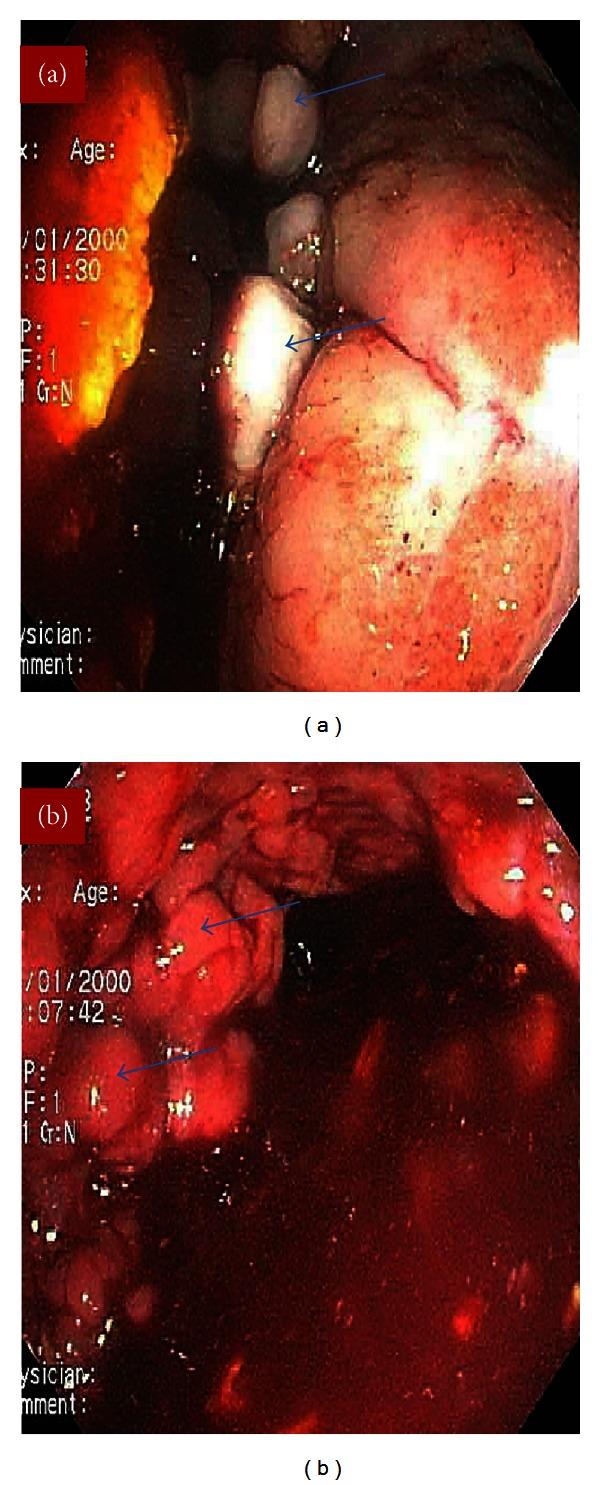

Klippel-Trenaunay syndrome (KTS) is a rare congenital syndrome of vascular malformations and soft tissue and bone hypertrophy. Vascular malformations can affect multiple organ systems. Involvement of the gastrointestinal (GI) tract is uncommon in KTS, but it can be a source of life-threatening bleeding. We report a case of a 32-year-old male with a known diagnosis of KTS who presented with a life-threatening rectal bleeding and was treated with proctosigmoidectomy and massive blood products transfusion. He expired after a long hospitalization. We then review the literature on KTS and management of some of its complications.

克-特综合征(KTS)是一种罕见的先天性综合征,伴有血管畸形以及软组织和骨骼肥大。血管畸形可累及多个器官系统。胃肠道(GI)受累在KTS中并不常见,但可能是危及生命的出血来源。我们报告一例32岁男性,已知诊断为KTS,因出现危及生命的直肠出血接受了直肠乙状结肠切除术和大量输血治疗。他在长期住院后死亡。我们随后回顾了关于KTS及其一些并发症处理的文献。